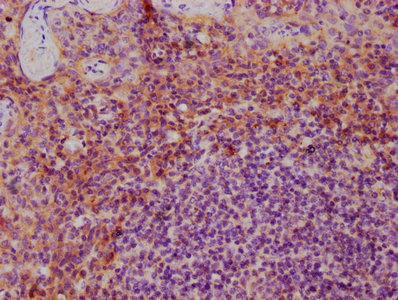

IHC image of CSB-PA06725A0Rb diluted at 1:600 and staining in paraffin-embedded human tonsil tissue performed on a Leica BondTM system. After dewaxing and hydration, antigen retrieval was mediated by high pressure in a citrate buffer (pH 6.0). Section was blocked with 10% normal goat serum 30min at RT. Then primary antibody (1% BSA) was incubated at 4°C overnight. The primary is detected by a biotinylated secondary antibody and visualized using an HRP conjugated SP system.

Application Recommended Dilution IHC 1:500-1:1000 -